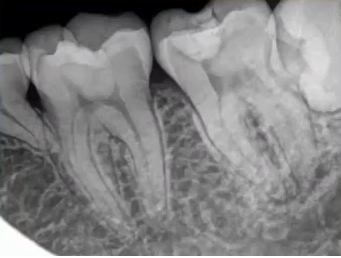

查:14残根,牙龈红肿;35叩诊(+),45叩诊(+),牙颌面见畸形中央尖。

35叩诊(+)

二次拍根尖片确认可看到根尖低密度炎症,临床检查与影像学检查相符,是根尖周炎。

曲面断层片怎么看口腔精读 | 一次性教你看懂曲面断层片!_https://www.jmylbn.com_新闻资讯_第21张

临床检查时发现14残根,牙龈红肿。曲面断层片上由于前磨牙转角问题,看不到残根,无法明确到底有没有残根,无法通过曲面断层片进行确诊或评估。

曲面断层片怎么看口腔精读 | 一次性教你看懂曲面断层片!_https://www.jmylbn.com_新闻资讯_第22张

这时需要加拍根尖片,很明显能看到残根。这就说明,有曲面断层片也不能排除情况。